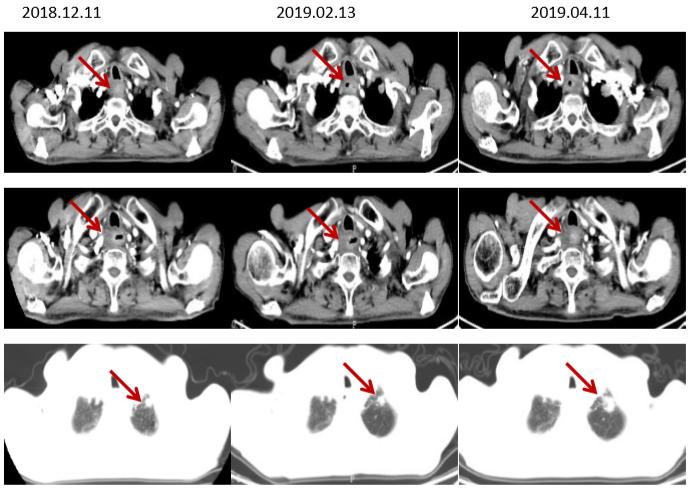

2019.02入院复查新发脑转移,余病灶稳定 。

MRI(2019.02.14)

右额叶可见类圆形长T1长T2信号,大小约20mm*23mm*23mm,边缘可见水肿带,DWI部分受限。

2019-02-21、2019-03-21继续 “IBI308”治疗2周期,回当地行脑部放疗(具体剂量不详)

CT(脑转移治疗前后食管病灶及肺转移灶对比,部分肺转移灶较前增大)